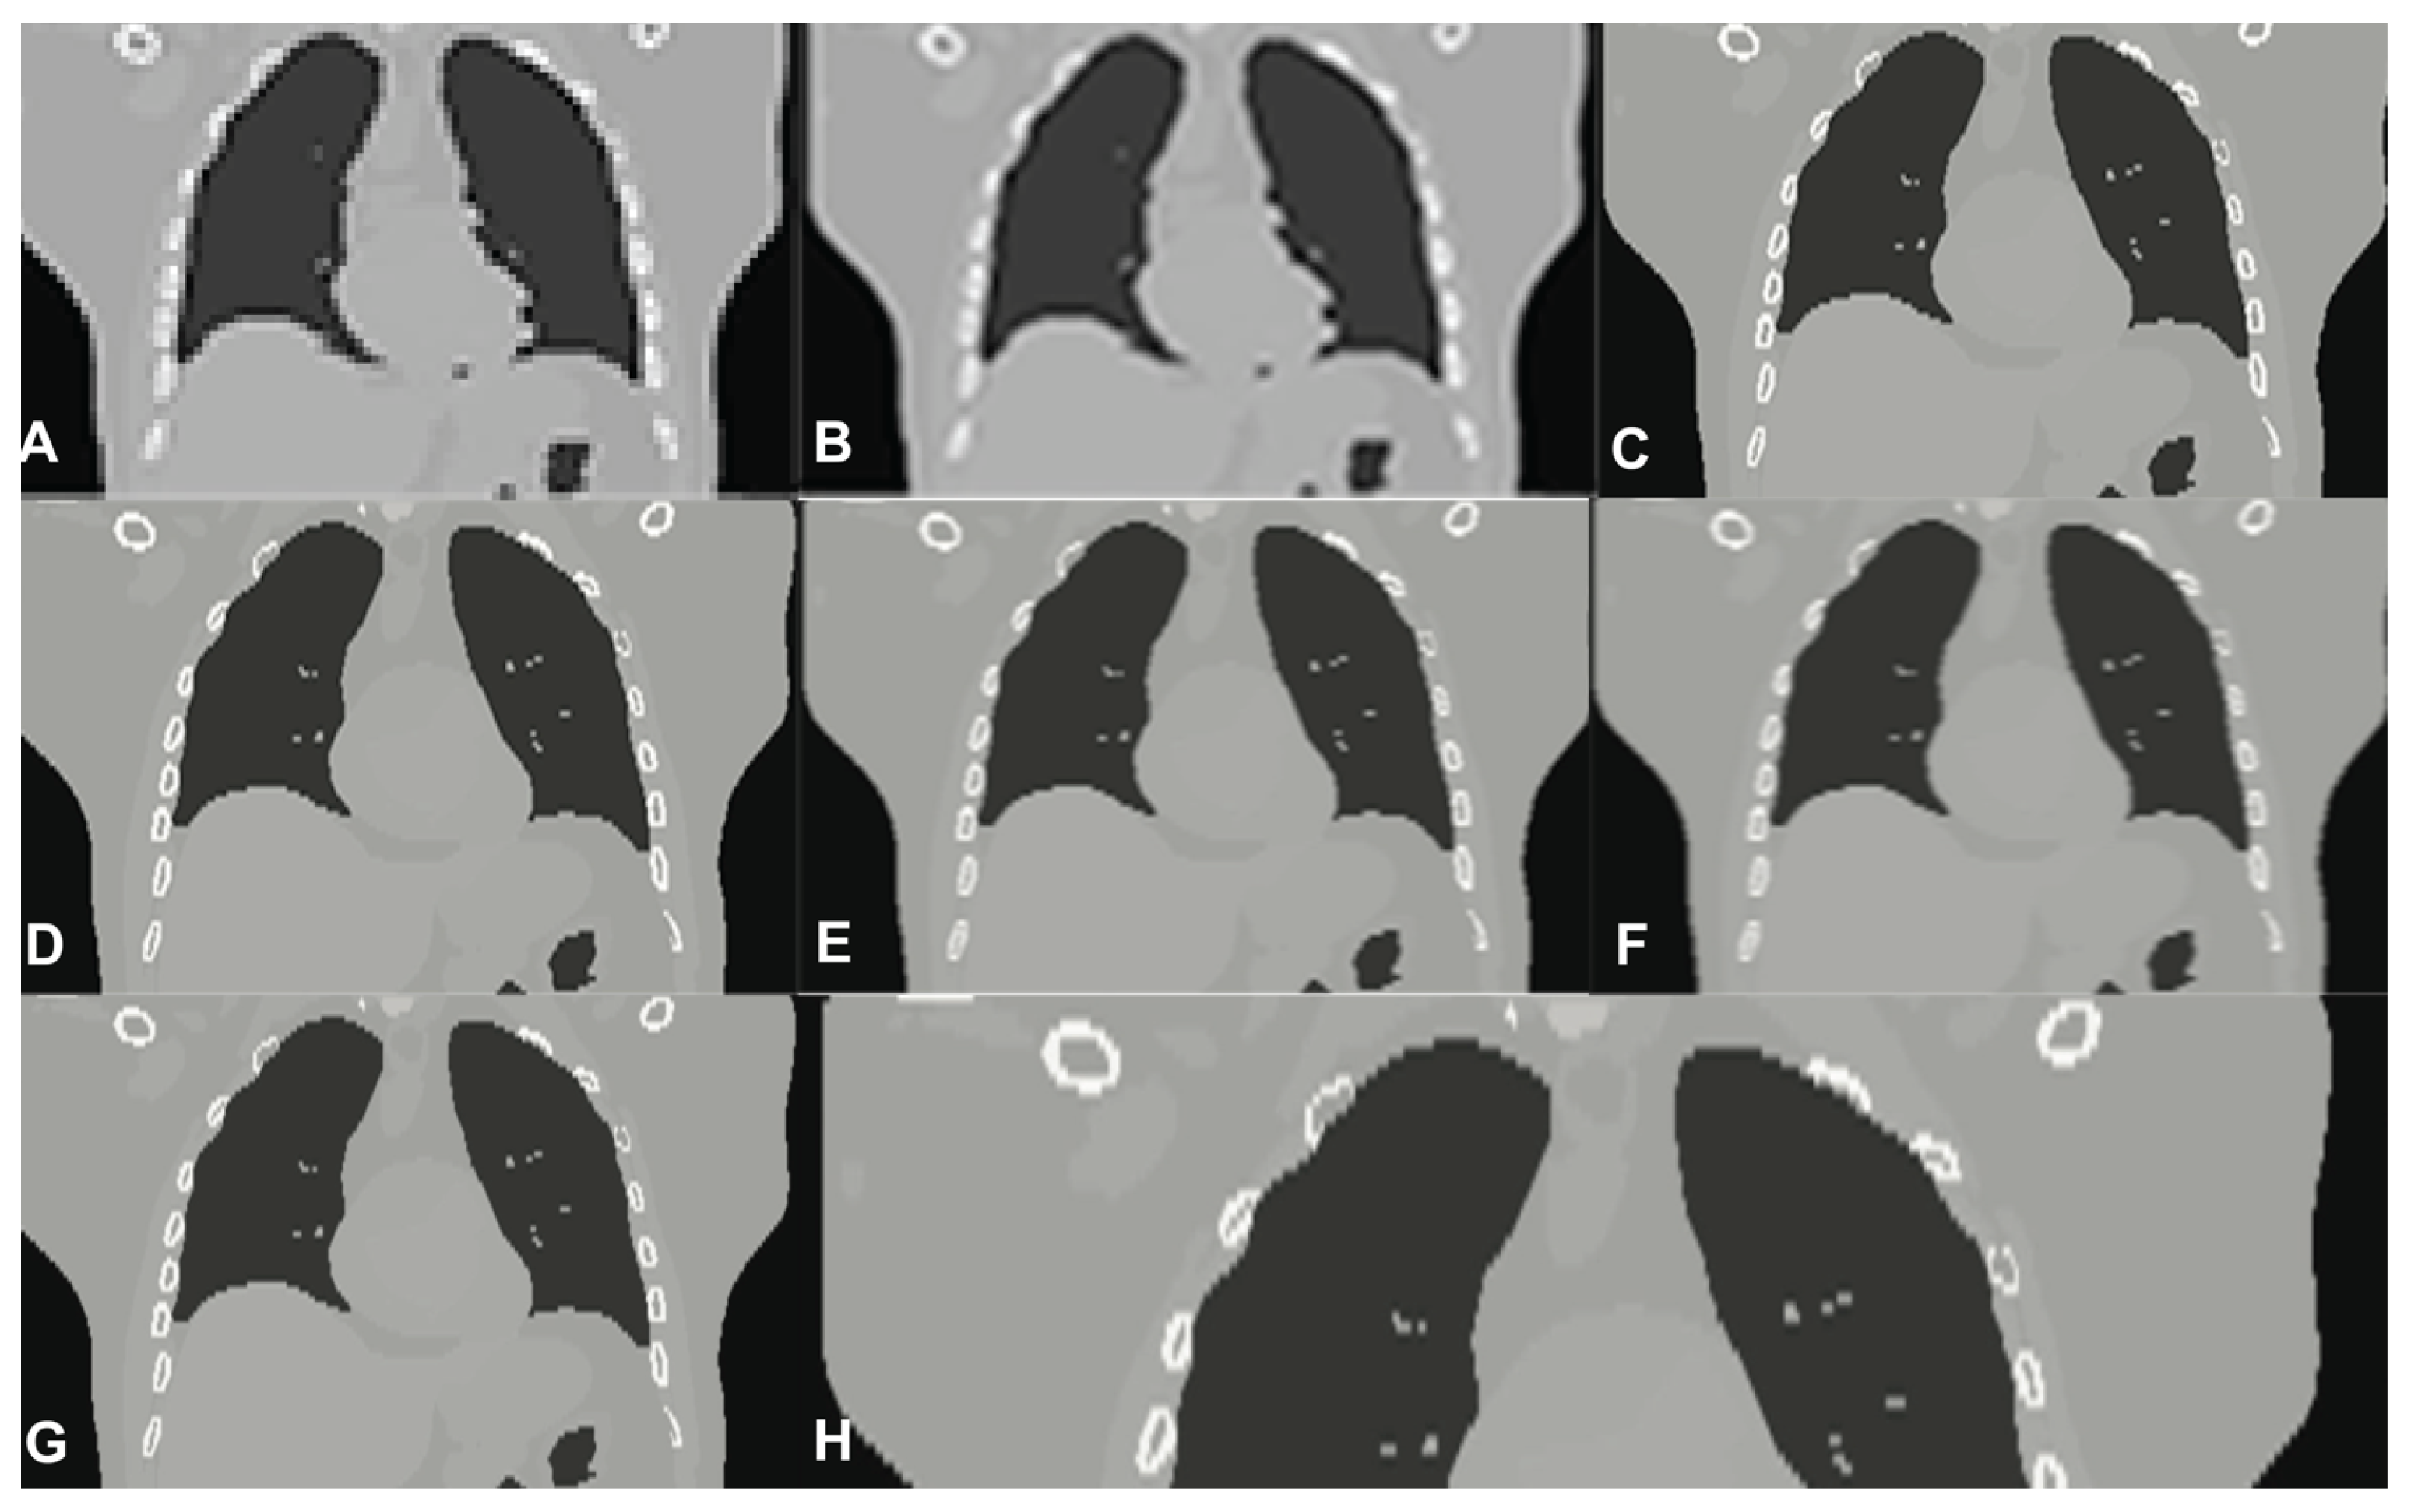

Figure 6.

CT low-resolution vs. Super-Resolution Images. (A) LR input; (B) B-spline Cubic interpolation; (C) Non-Rigid Multi-Modal 3D Medical Image Registration Based on Foveated Modality Independent Neighbourhood Descriptor [25]; (D) Enhanced deep residual networks for single Image Super-Resolution [13]; (E) Image SR using very deep residual channel attention networks [14]; (F) Residual dense network for image SR [15]; (G,H) the presented algorithm (the right one exposes details). (The tests were performed using 4096 Projection lines/Coefficients and the ATA reconstruction algorithm).